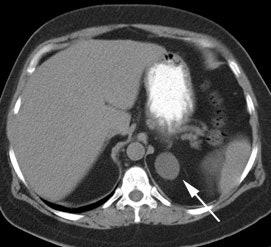

Unsuspected bone metastases: The patient shown below had a cavitary left lung non-small cell lung cancer. There was no uptake of tracer within the aortopulmonary window lymph nodes detected on CT to suggest metastases, however, unsuspected bone metastases were found in the left anterior 4th rib (black arrow) and lumbar spine (red arrows- not included in staging lung CT scan). The presence of bone metastases significantly alters patient prognosis and management. PET imaging provides a rapid whole body survey for the detection of unsuspected metastatic disease. |

|